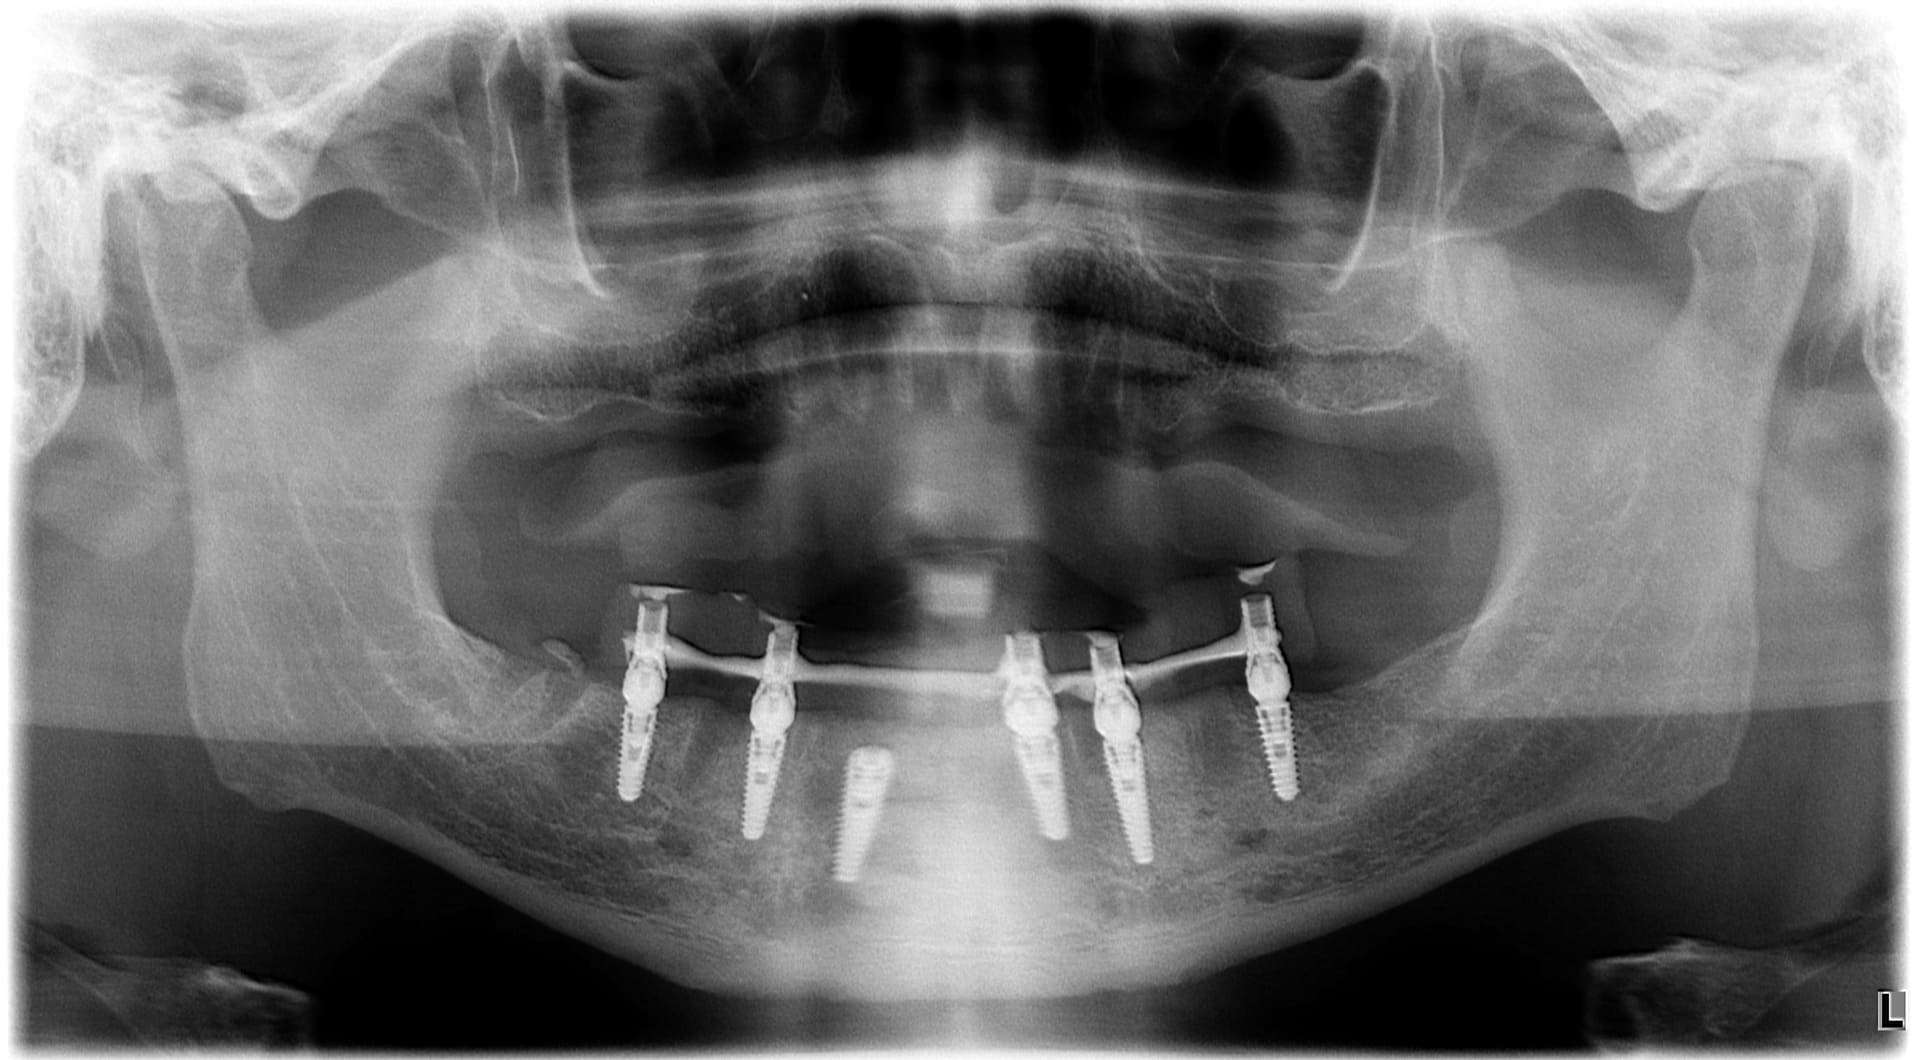

Paziente 2

Dopo >